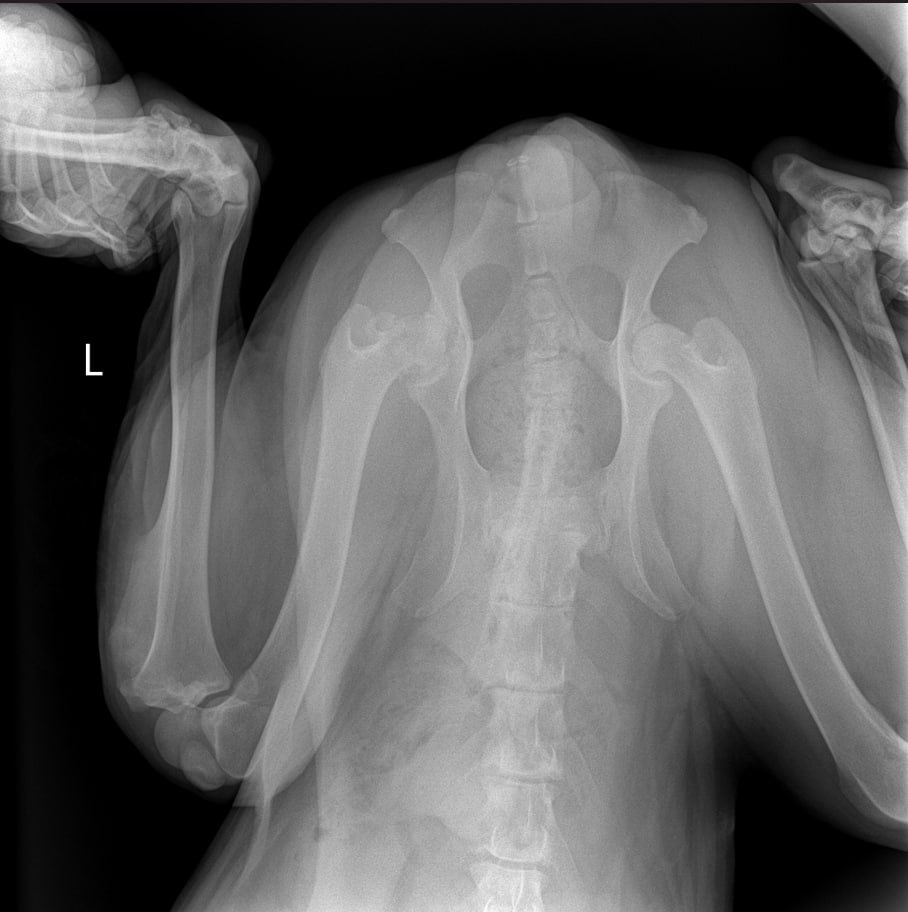

Рентген

Описание рентгена